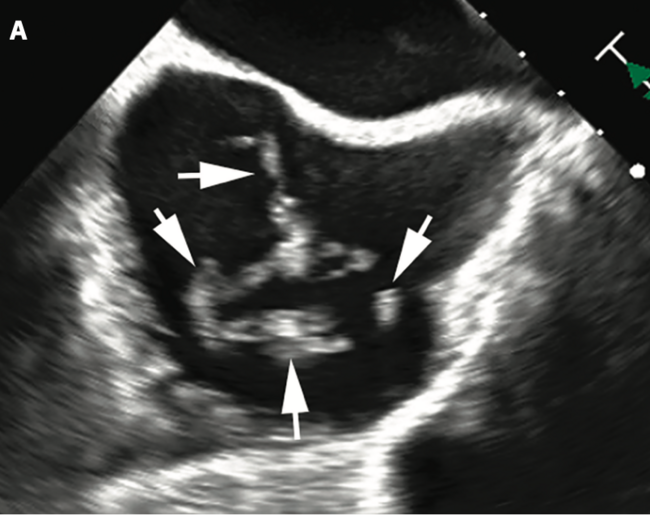

An 84-year-old woman was brought to the emergency room with lightheadedness and shortness of breath that had started 3 days earlier. She had a past medical history of paroxysmal atrial fibrillation, hypertension, and coronary artery disease. She was not on anticoagulation due to medication non-compliance. On presentation, her vitals were: heart rate 150-200/min, blood pressure 129/99 mmHg, respiratory rate 19/min, and oxygen saturation on room air 99%. Physical exam was unremarkable. Electrocardiogram showed atrial fibrillation with rapid ventricular response at 189/min. Cardiac biomarkers were negative. She was initially treated with intravenous beta blockers and calcium blockers and due to inadequate response, urgent cardioversion with transesophageal echocardiography (TEE) was planned. TEE showed a large, mobile thrombus swirling in the right atrium (thrombus in transit) (Figure 1A). There was no left atrial appendage thrombus or interatrial shunt. As a result, cardioversion was postponed and she underwent emergent percutaneous mechanical thrombo-embolectomy with Inari FlowTriever 20 (Inari Medical) to aspirate thrombus from the right atrium under intra-cardiac echocardiography (ICE) guidance (Figure 1B). After one successful aspiration, ICE did not identify more thrombus in the right atrium and adjacent vena cava (Figure 1C). A serpentine thrombus was successfully aspirated (Figure 1D).